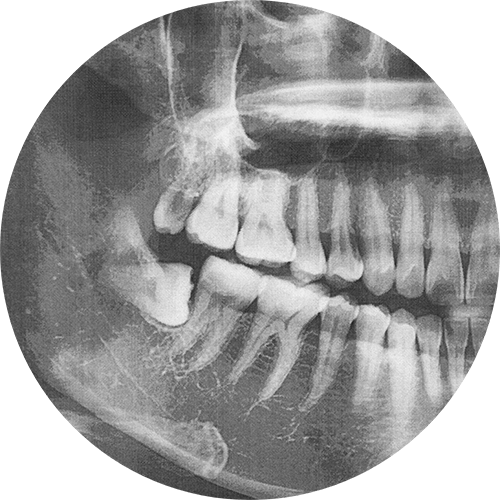

The wisdom teeth, sometimes referred to as the third molars, are the last set of teeth to erupt at the back of the mouth, normally between the ages of 17 and 25. However, most people actually end up needing theirs removed since there often isn’t enough room inside the mouth for them to erupt properly. This has led to wisdom tooth extraction becoming one of the most commonly performed oral surgeries, and we’re more than happy to provide this service for your child or loved one here at our Las Vegas dental office. To learn more or schedule a consultation, please reach out to our Advent Dental team.

The wisdom tooth extraction process is very straightforward and routine, and remember—it’s designed to remove these teeth before they can cause painful crowding, infections, or other issues. The process begins with your mouth being numbed, and sedation is often also used to ensure full comfort. From there, the gum tissue is gently opened up, and the teeth are carefully removed, often in sections to minimize irritation and make things easier. You might feel some pressure, but no pain whatsoever during the procedure. Once the teeth have been removed, the surgical sites are cleaned and sutured if needed, and most patients recover quite quickly with simple aftercare and minimal discomfort.